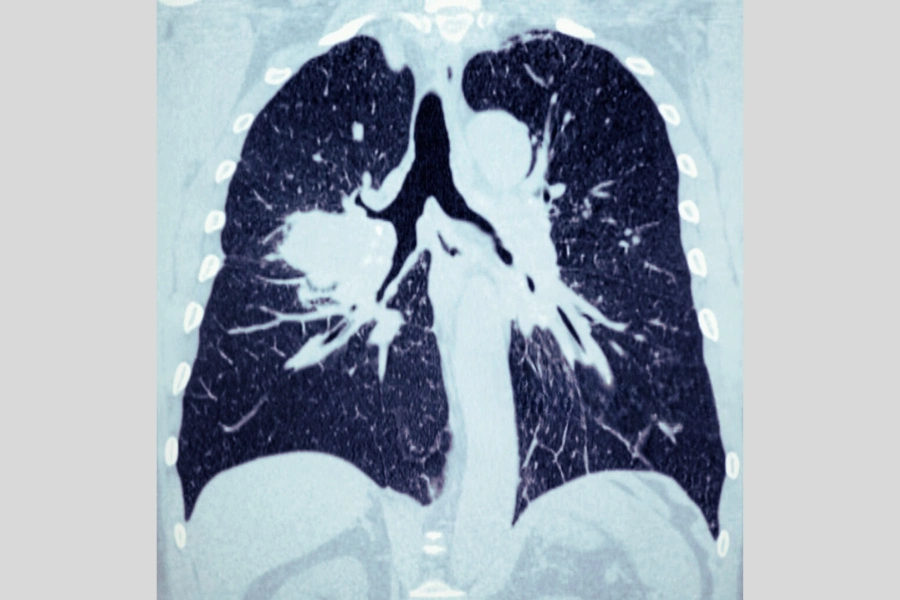

КТ легень при підозрі на пневмонію чи онкологію

Під час обстеження комп’ютерна томографія показує ділянки запального інфільтрату — це місця, де альвеоли заповнені рідиною, слизом або гноєм замість повітря. Завдяки високій роздільній здатності зображення лікар може чітко побачити форму, межі та поширення ураження. При бактеріальній пневмонії зазвичай спостерігаються щільні, однорідні затемнення в межах однієї частки легені, тоді як при вірусному або атиповому запаленні інфільтрати мають дрібновогнищевий або сітчастий характер, розташований у кількох сегментах.

КТ легень при пневмонії дозволяє також виявити накопичення рідини у плевральній порожнині, яке може свідчити про ускладнення у вигляді плевриту. Часто фахівець бачить на знімках ділянки ателектазу — зони спадання легеневої тканини, що виникають через порушення вентиляції. Крім того, томографія дає можливість відрізнити гострий запальний процес від хронічних змін, наприклад фіброзу, що залишаються після попередніх інфекцій.

Онкологічні захворювання легень тривалий час можуть розвиватися без будь-яких виражених симптомів. Саме тому КТ при раку легень є одним із найважливіших інструментів для ранньої діагностики злоякісних пухлин. Комп’ютерна томографія дозволяє виявити навіть найдрібніші утворення розміром у кілька міліметрів, визначити їхню щільність, форму, межі та глибину проростання у тканини. Ці параметри є критично важливими для того, щоб відрізнити доброякісне утворення від злоякісного.

Крім первинного раку, КТ легень часто виявляє метастази — вторинні пухлини, що потрапили до легень з інших органів, наприклад, молочної залози, кишечника або нирок. На знімках метастази виглядають як множинні вузлики різного розміру, розкидані по легеневій тканині. Їх наявність свідчить про поширення злоякісного процесу і саме комп’ютерна томографія є основним методом для оцінки обсягу ураження та контролю ефективності лікування після хіміо- або променевої терапії.